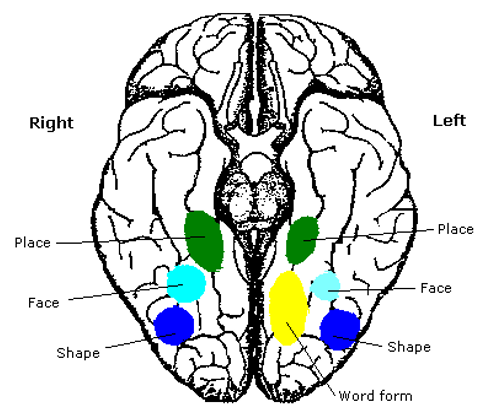

Gyral anatomy of inf occipitotemporal surface: The inf. temp. gyrus wraps from lateral https://abs.twimg.com/emoji/v2/... draggable="false" alt="➡️" title="Pfeil nach rechts" aria-label="Emoji: Pfeil nach rechts">inferior. The fusiform and lingual gyri span from occipital lobe posteriorly to temporal lobe anteriorly. Parahippocampal is medial temporal (anterior continuation of the lingual g).

https://abs.twimg.com/emoji/v2/... draggable="false" alt="➡️" title="Pfeil nach rechts" aria-label="Emoji: Pfeil nach rechts">inferior. The fusiform and lingual gyri span from occipital lobe posteriorly to temporal lobe anteriorly. Parahippocampal is medial temporal (anterior continuation of the lingual g).

The lingual gyrus is involved in holistic visual and word processing, encoding visual memories, imagery, and dreaming. The ganglioglioma in the shown case is centered in the lingual gyrus.

Fusiform g is just lateral to lingual g on the inf surface of temporal lobe, separated by collateral sulcus. It& #39;s medial to the ITG, separated by ITS. Involved in face and body recognition; word form recognition (on left). (Fusiform g was not definitively involved by tumor). 9/13

Parahippocampal g. is anterior continuation of lingual g. Part of Limbic System. Important in memory encoding and retrieval, visual and social contextualizing.

Some functional #neuroscience: Inf temp lobe is involved in higher order visual processing along the ventral stream (the "what is it" path of visual sensory processing https://abs.twimg.com/emoji/v2/... draggable="false" alt="➡️" title="Pfeil nach rechts" aria-label="Emoji: Pfeil nach rechts"> color/object/word/face/body perception/recognition/identification, & associated cognitive functions)

https://abs.twimg.com/emoji/v2/... draggable="false" alt="➡️" title="Pfeil nach rechts" aria-label="Emoji: Pfeil nach rechts"> color/object/word/face/body perception/recognition/identification, & associated cognitive functions)